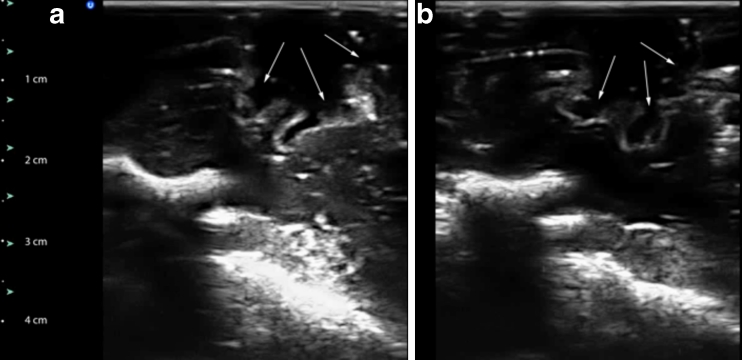

Fig. 5.

Resection cavity (marked with arrows) made in a fresh piglet brain, imaged using physiological saline to fill the resection cavity (a) and imaged using the developed acoustic coupling fluid (b). The acquisition parameters are identical in both cases. The dominating signal enhancements in the deeper part of the images are caused by strong reflections from the scull base. Note the difference in intensity below the resection cavity in the two images. Even if the slice orientation is not perfectly identical in the images, it is apparent that there is no artificial signal enhancement directly below the bottom of the resection cavity in b. The difference in signal intensity can also be seen in the deeper bone reflections in a and b